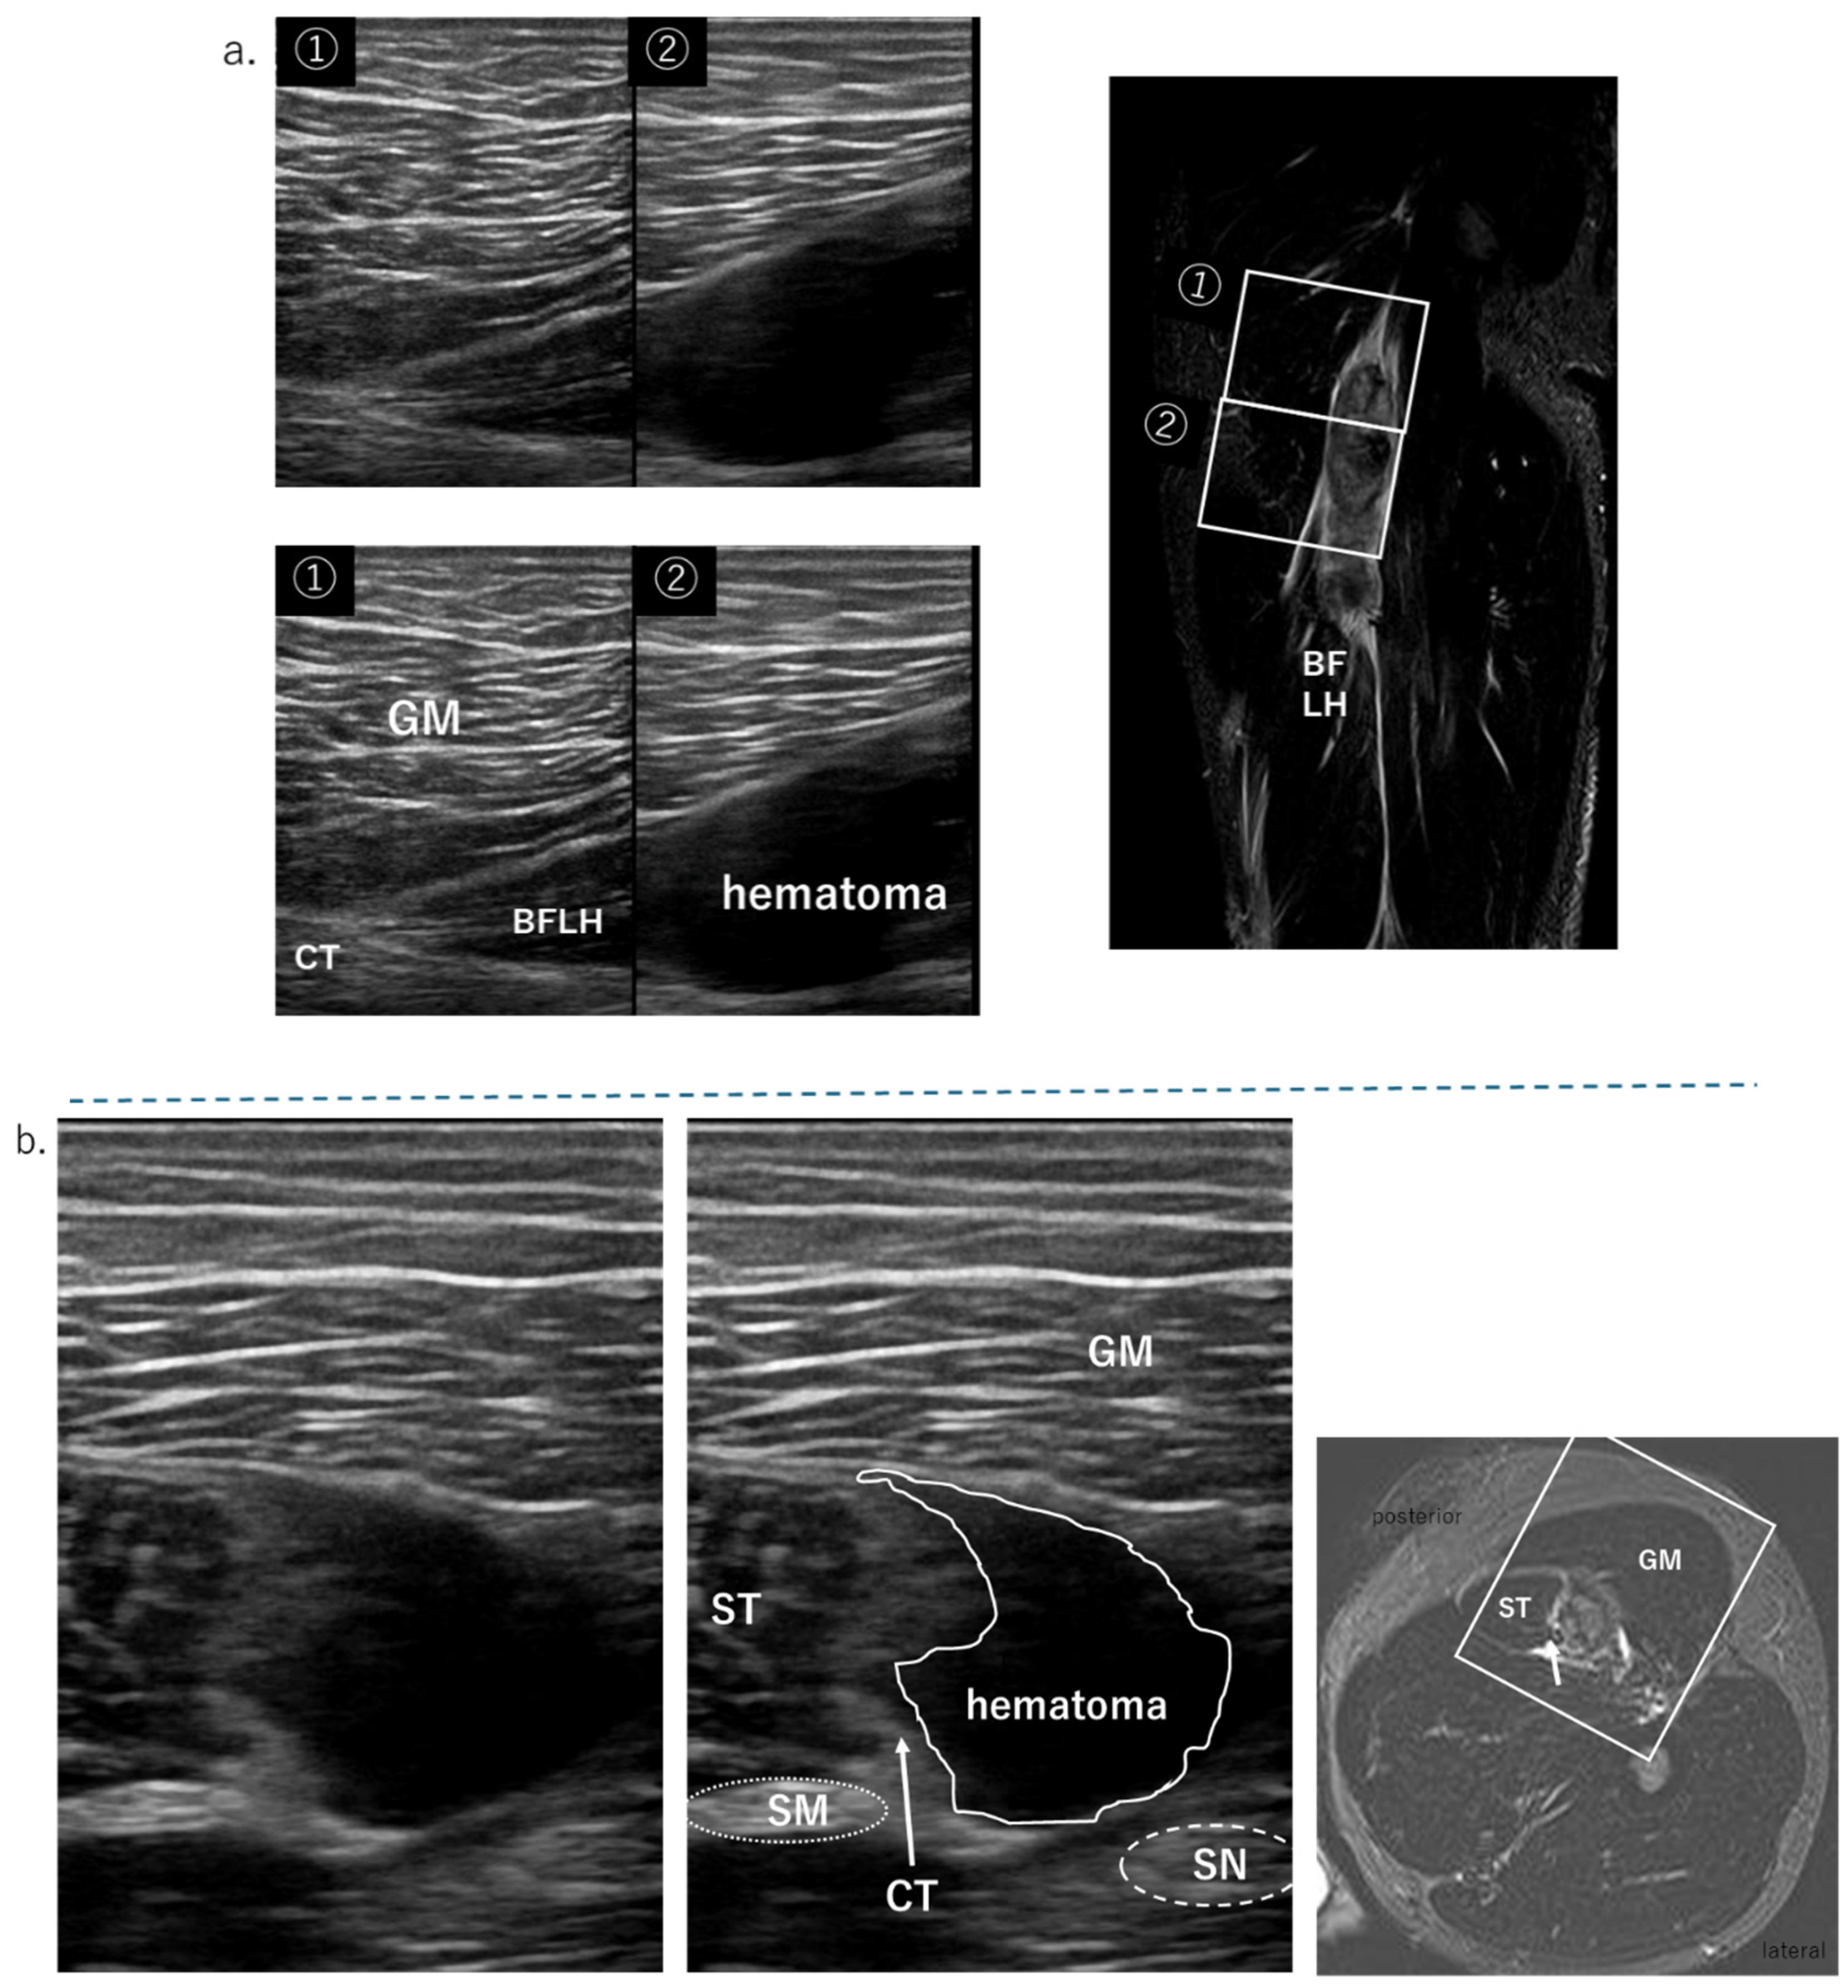

4.3. Proximal Tendon—Musculo Tendinous Junction

Injuries extending from the proximal CT of the ST and BFLH to the myotendinous junction are also very common [3,8]. A full-thickness injury to the free tendon of the BFLH will result in a hematoma on both the ST and BFLH sides. As the severity of the muscle tear increases, the tension at the periphery of the torn area decreases, and it becomes tortuous (Figure 6). In the case of an ultrasound short-axis image, if the surrounding hematoma in the CT is large, it can be detected, but if the hematoma is small, it is difficult to detect, and diagnosis is performed together with MRI. It is easy to detect those with torn CTs that had retracted distally in the long-axis view. In addition, for damage to the myotendinous junction, if the continuity is clearly lost, it can be determined in the long-axis view, but if the damage is slight, it is necessary to check with MRI. In this study, it was difficult to detect microscopic injuries without hematomas, especially those at the myofascial junction (MFJ), using ultrasonography.

4.4. Biceps Femoris Tear

Figure 6. The US findings of the CT tear, MRI condition: T2-weighted image with fat suppression. (a) short-axis view at level 1, CT rapture and hematoma; (b) short-axis view at level 2, tortuosity CT (yellow arrow), and ST side hematomas, BFLH side hematomas; (c) long-axis view, CT dropped to the periphery (yellow arrow) due to CT rupture. Refer to the sagittal MRI image.